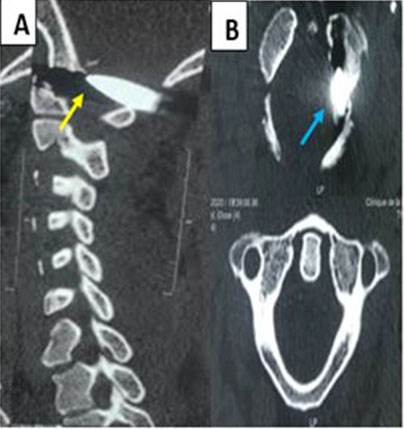

Figure 3: Cervical CT scan, (A) axial slice, (B) sagittal reconstruction: showing the presence of a projectile at the level of the left occipito-atloid joint with fracture of the internal cortex of the ipsilateral condyle (yellow and blue arrow).

Share Image:

We report the case of a 16-year-old patient from Guinea (Conakry), with no particular pathological history residing in the Medina that we had received two (02) months from a ballistic trauma of the upper cervical spine that occurred in Guinea Conakry. She allegedly received a projectile (gun bullet) in her home during an armed attack in her neighborhood at around 4 a.m. She presented with stiff neck with no other associated signs. The general examination revealed: a general satisfactory condition, skin and mucous membranes well colored, no edema of the lower limbs, nor folds of dehydration. The weight was 45 kg, the height 1.50 meters, the temperature 37.1 °C, the frequency: 90 beats/min, and the respiratory rate: 22 cycles/min. On neurological examination: walking was normal, there were no sensory-motor deficits nor genito-sphincter disorders. Examination of the spine revealed kyphosis of the cervical spine with contraction of the para-vertebral muscles on palpation. At the cephalic end, we noted the presence of a wound in the process of vertical healing, about 5 cm long, located at the level of the left posterolateral face of the neck, corresponding to the entry orifice of the projectile (Figure 1). The blood crisis was normal. The standard cranio-cervical radiography had objectified the presence of a projectile at the level of the occipito-atloid joint (Figure 2). Cranio-cervical computed tomography which revealed the presence of a projectile at the level of the left occipito-atloid joint with fracture of the internal cortical bone of the ipsilateral condyle (Figure 3). The aim of the surgery consisted of a cervical laminectomy associated with a withdrawal of the projectile (Figure 4) at the level of the condylo-atloid junction and an exploration in search of vascular complications (damage to the vertebral artery) and osteomeningeal breaches (dural lesion) that we had not detected during the operation. Wearing a C4 collar for a minimum of 3 or 4 months was associated. Postoperative parenteral treatment with amoxicillin-clavulanic acid (1 g × 2/d in direct intravenous (IVD)), hydrocortisone hemisuccinate (100 mg × 2/d in IVD= direct intravenous) and analgesics at a rate of 60 mg/kg weight divided into four doses are prescribed for four days, with an oral relay for eight days. The operative consequences were simple. The operative outcome was simple. The patient was seen again one month after surgery without any clinical particularity.